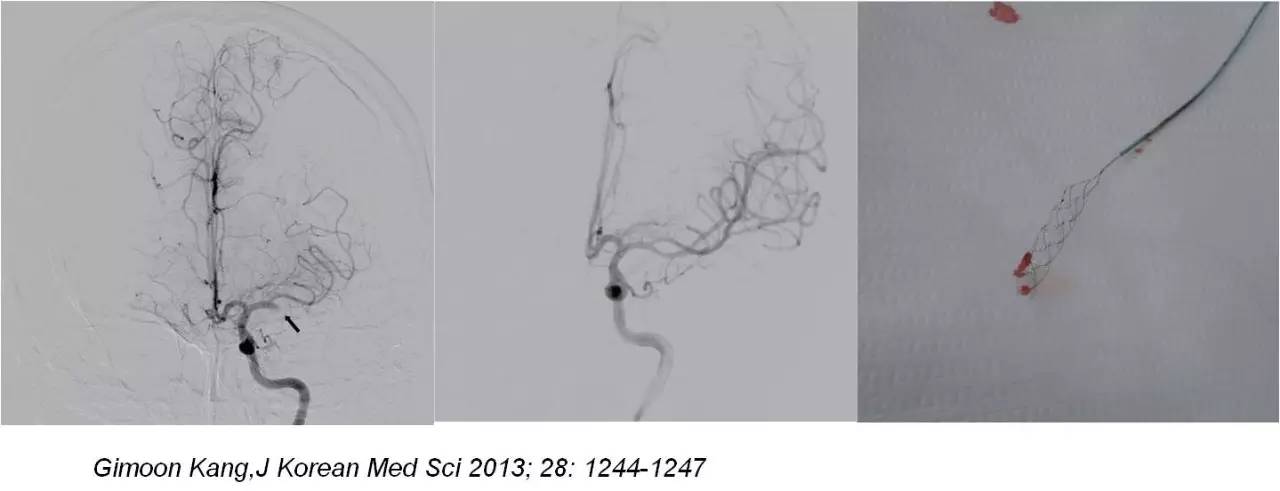

》右侧腹股沟区局部浸润麻醉,常规造影,发现闭塞责任血管后,将微导丝及微导管在导引导管辅助下置于闭塞血管近心端,经微导管注射rt-PA 10-30mg,10min后造影观察血管再通情况 。

》若无再通,微导丝缓慢推进通过闭塞血管,微导管跟进,造影观察闭塞血管远端血管情况,若远端血管通畅,选用取栓支架(Solitaire-AB;ev3 公司,美国)。

》男性,47岁,SIE;

》UCG:主动脉瓣关闭不全,赘生物;

》突发言语不能、右侧肢体活动不能;

》查体:运动性失语,右侧肌张力低,右侧肌力0级,右侧巴氏征阳性 。NIHSS评分18分;

》CT:颅内未见出血;

》DSA:左侧大脑中动脉闭塞。

术后

》意识清楚,言语流利,四肢活动自如;

》四肢肌力Ⅴ级;

》术后24小时NIHSS评分:0分;

》5天后主动脉换瓣术;

》90天mRS评分0分。

mechanical embolectomy in cases of troke due to infective endocarditis manifesting with major neurologic deficits is a subject of controversy and needs additional clinical experience and evaluation in a randomized trials.

取栓治疗对脑梗死所致严重神经功能障碍的疗效需要:

#进一步的临床经验积累

#高质量的随机对照研究